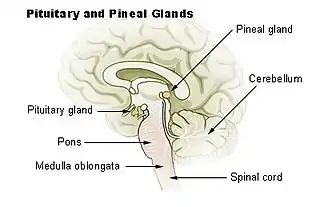

Diagrama de las glándulas pituitaria y pineal, en el encéfalo humano (nomenclatura en inglés). | ||

Estructura

La glándula pineal es de color gris rojizo y del tamaño aproximado en los seres humanos de un grano de arroz (5-8 mm), se encuentra justo en el rostro dorsal al colículo superior, detrás y por debajo de la estría medular, entre los órganos del tálamo colocados lateralmente. Es parte del epitálamo. Se encuentra ubicada en la cisterna cuadrigémina y está bañada en el líquido cefalorraquídeo. Un pequeño receso pineal del tercer ventrículo se proyecta hacia el tallo de la glándula. La glándula pineal es una estructura de línea media en forma de cono de pino.